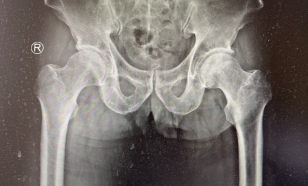

术前

通过病情描述结合磁共振检查结果,蒋守海主任诊断刘大叔为“股骨头坏死”。考虑到刘大叔的年龄、疼痛程度及髋关节功能情况,蒋主任建议他进行人工髋关节置换手术治疗,一听要手术,大叔有点慌。

第二天蒋主任手术团队就为大叔准备“左全髋关节置换术”,从左髋前侧进入,沿阔筋膜张肌与股直肌间隙进入,切开关节囊,见股骨颈出现囊性变,股骨头有塌陷,将股骨颈与股骨头取出,并对髋臼进行磋磨,以适配髋臼假体,使用螺钉固定后置入假体,复位关节,对关节的屈伸、收展及旋转情况进行检查,关节稳定,手术顺利结束。